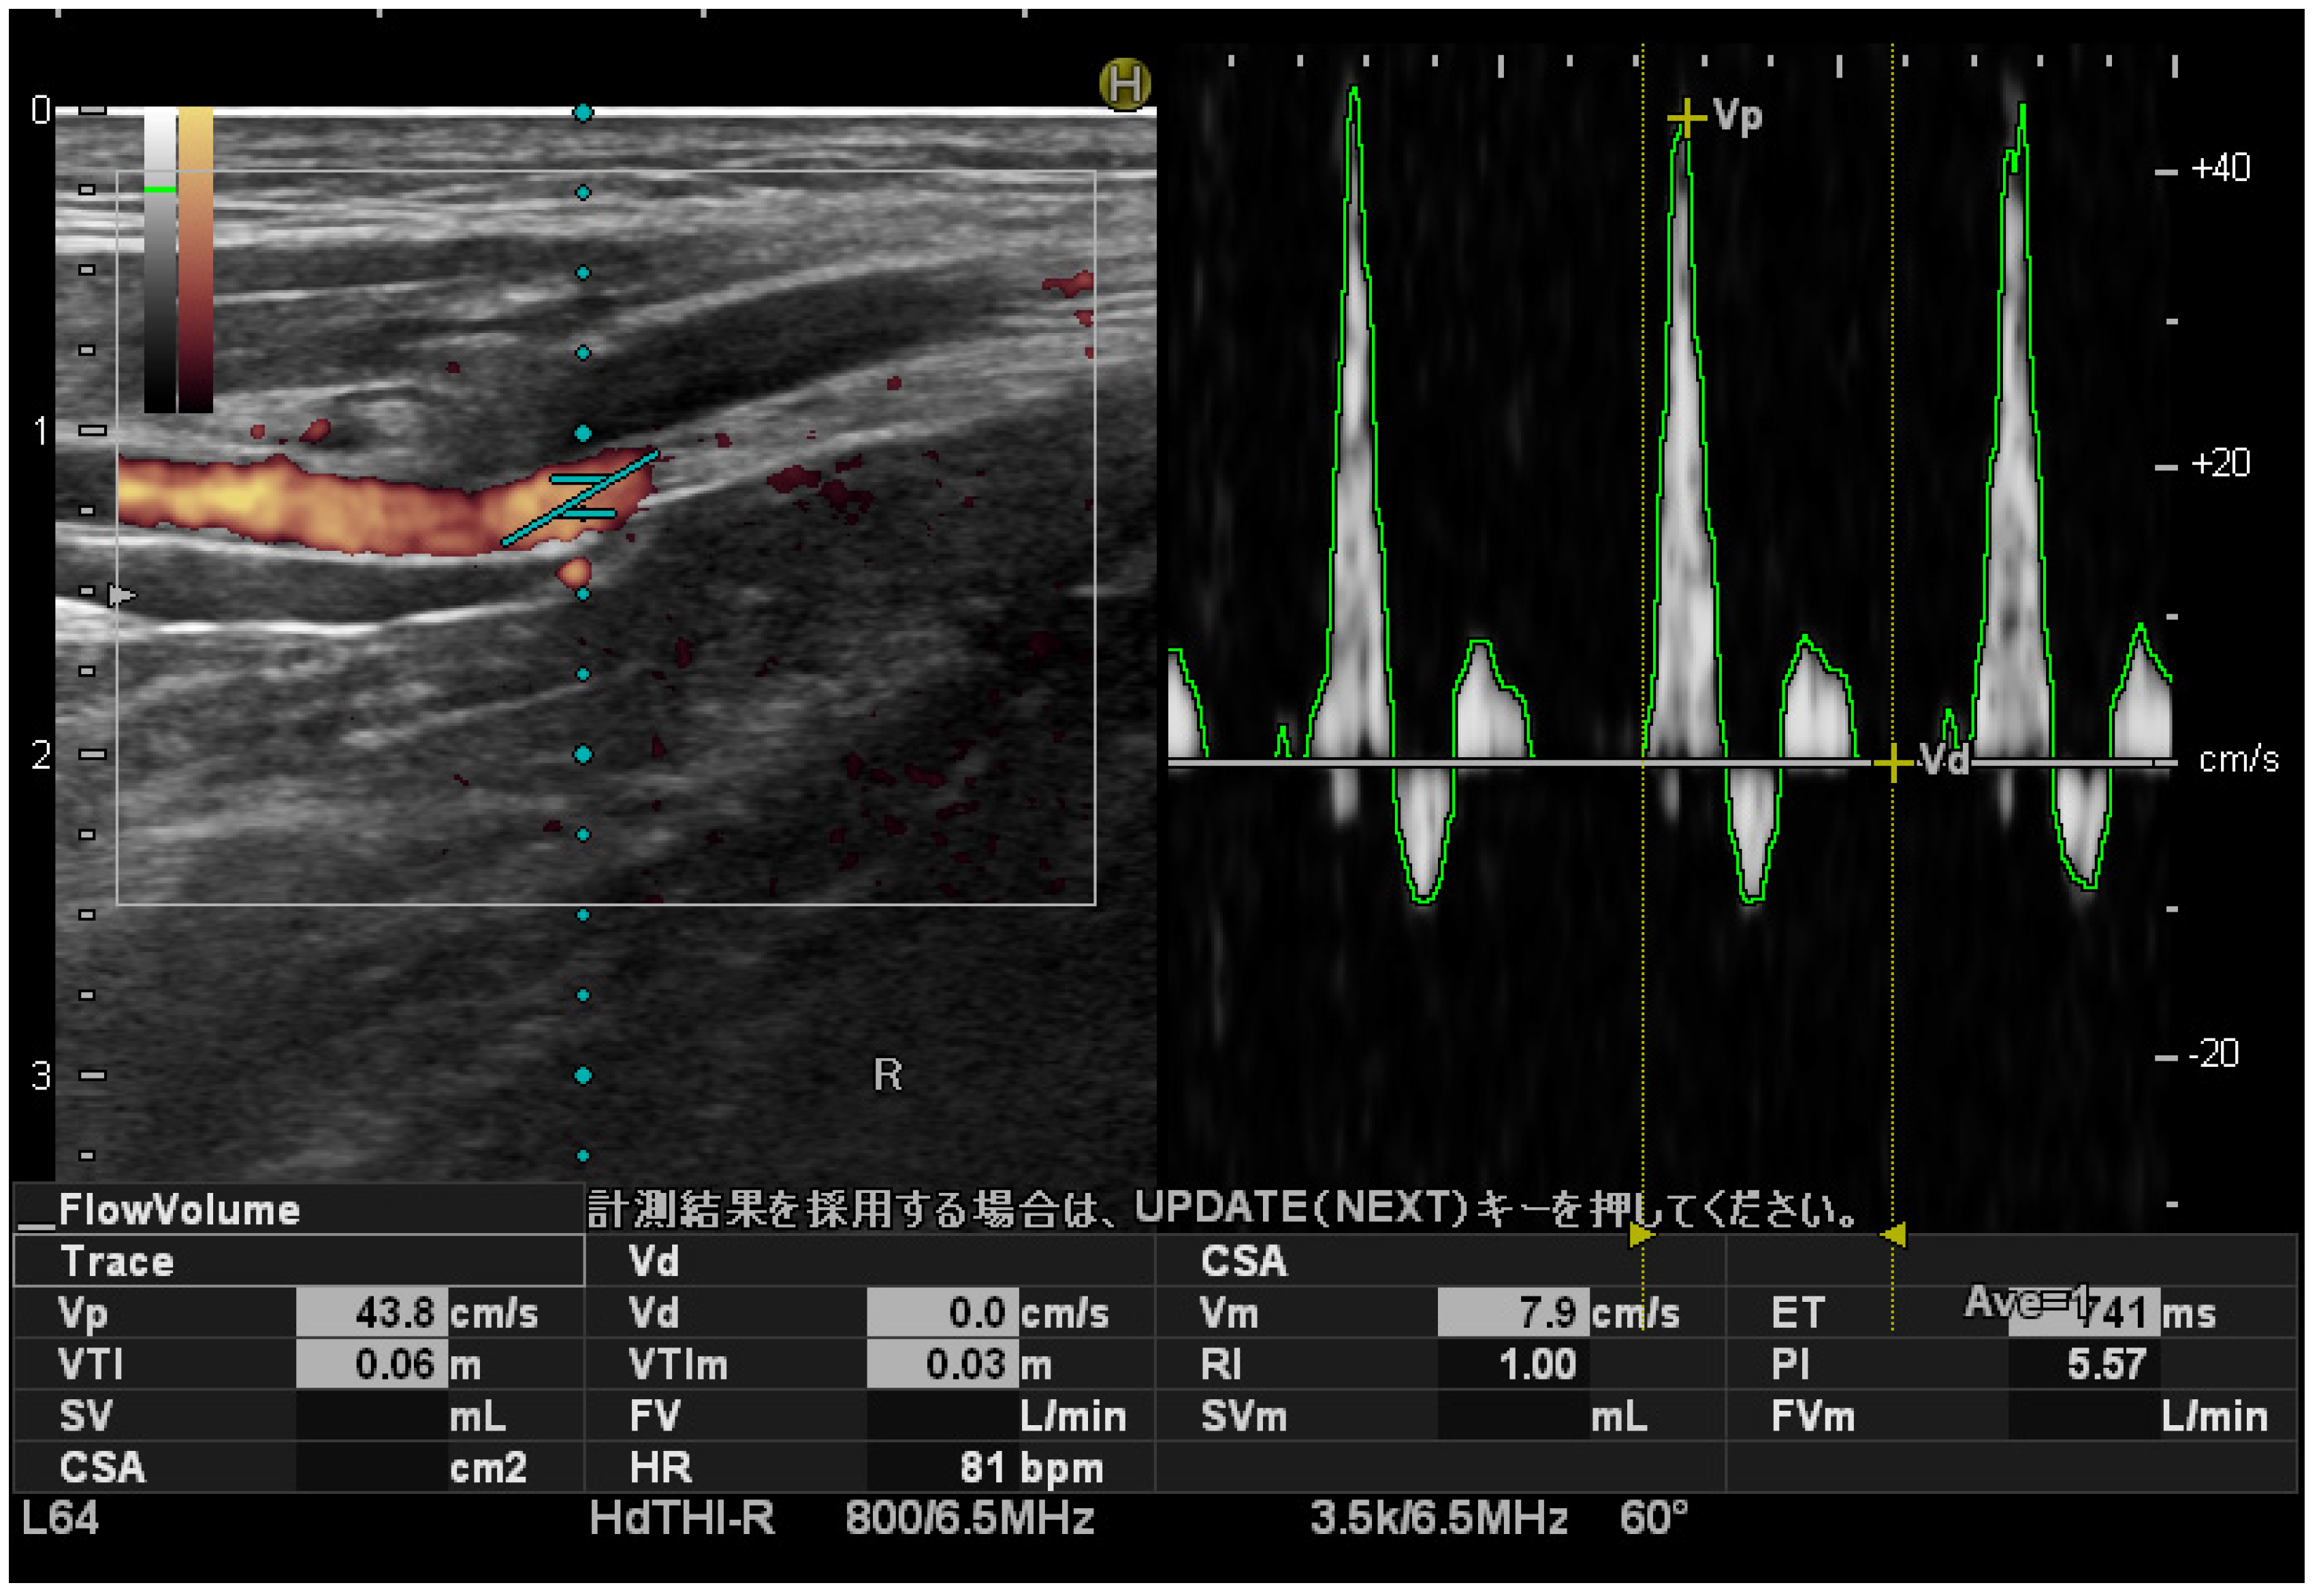

2.2. Settings of the Measuring Equipment

2.3. Measuring PTA Blood Flow Velocity